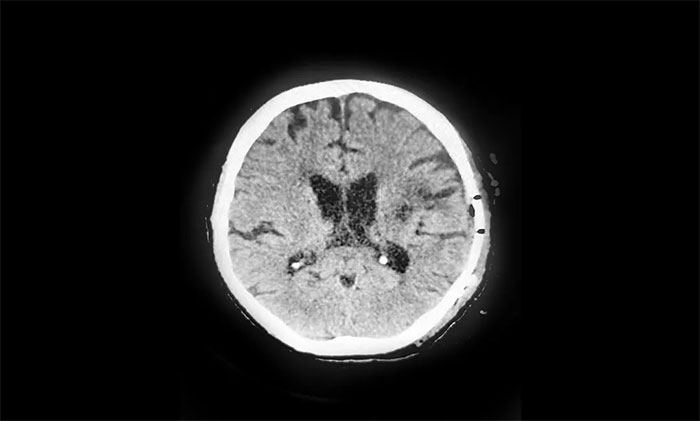

▲ 術(shù)后影像顯示“復(fù)原”后的顱骨

吳太太知道,顱骨缺損對(duì)丈夫影響很大,他隨便動(dòng)一下、咳嗽一聲,缺損部位都會(huì)隨之移動(dòng)。日常生活中也讓人沒(méi)有安全感,而且影響容貌,還要擔(dān)心其他并發(fā)癥的可能。夫妻二人百般合計(jì),決定在出院前完成顱骨修補(bǔ),如此才能徹底心安,一勞永逸。

潘仁龍主任也十分贊同吳先生夫婦的決定。他從臨床醫(yī)學(xué)方面談到,當(dāng)缺損范圍直徑超過(guò)3cm時(shí),特別是位于額部,不僅影響患者形象美觀,而且嚴(yán)重危害患者身心健康,需及時(shí)進(jìn)行顱骨修補(bǔ)術(shù)。

經(jīng)過(guò)審慎評(píng)估,1月17日,潘仁龍主任、吳治群博士帶領(lǐng)醫(yī)護(hù)團(tuán)隊(duì)為吳先生順利實(shí)施了顱骨修補(bǔ)術(shù)。術(shù)后,經(jīng)過(guò)10天的恢復(fù),吳先生已于日前康復(fù)出院。